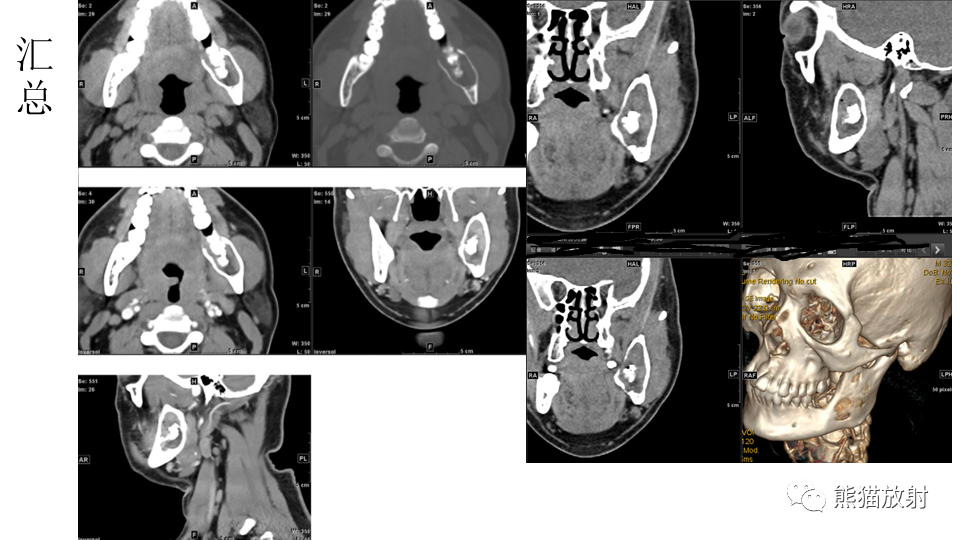

【病例】下颌骨成釉细胞瘤2例CT-5

【病例】下颌骨成釉细胞瘤2例CT-6

【病例】下颌骨成釉细胞瘤2例CT-7